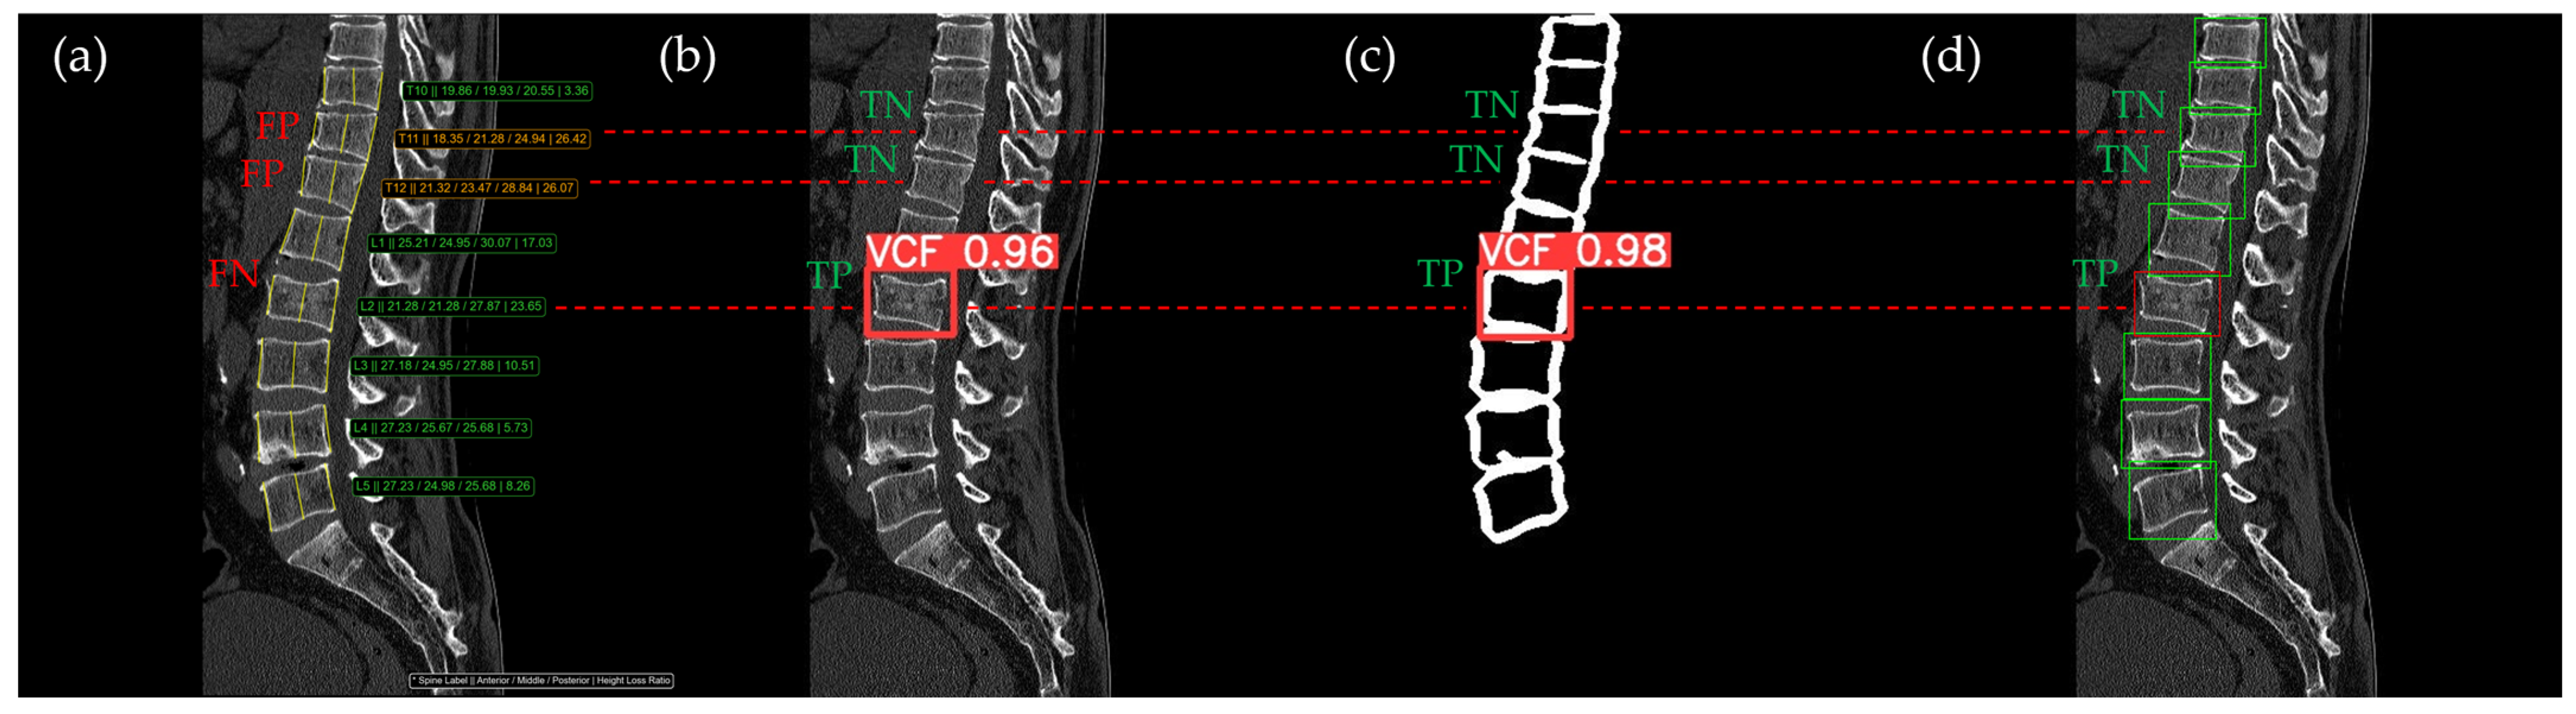

Figure 10, Figure 11, Figure 12, Figure 13 and Figure 14 illustrate typical examples of results for HLR, EEVD, TSVD_SD, and TSVD_DC in patients with acute VCFs. The results of applying different methodologies to the same patient image and identical slice locations were as follows. In the HLR results, each vertebra was marked with yellow solid lines indicating the height measurement lines for the anterior, middle, and posterior regions. The measured height values and HLR percentages were displayed on the right side of the image. If the HLR percentage ranged between 25% and 40%, it was highlighted in orange, while values of 40% or higher were highlighted in red. In the EEVD results, the VCF detection outputs were displayed along with their respective confidence scores based on the input patient images. For the TSVD_SD results, after performing spine segmentation, the model extracted only the spine contour, and the VCF detection results with their corresponding confidence scores were presented. In the TSVD_DC results, bounding boxes were generated for each vertebral body, with normal vertebrae represented in green and vertebrae identified as VCFs displayed in red.

The VCF detection results from four different methods. (a) HLR, (b) EEVD, (c) TSVD_SD, and (d) TSVD_DC. The acute VCF, as confirmed by the radiologist, was located at the L2 level. Both the FN and TP were marked at the same level with a red dotted line.

In Figure 10, the acute VCF was present only at the L2 level, characterized by morphological features of an anterior cortical step-off. With the HLR method, the result was an FN, whereas EEVD, TSVD_SD, and TSVD_DC correctly identified it as a TP.